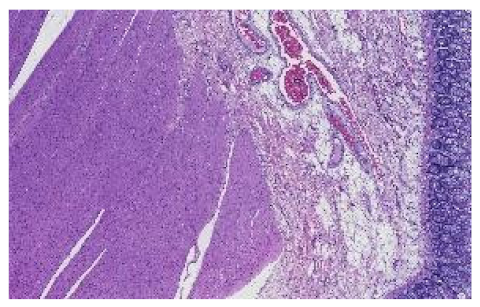

The preprocessing stage began with 66 WSI scans; we digitally cropped one region of interest (ROI) of size 1440 × 904 pixels for each tissue type in each slide. This resulted in three sets of images of 66 ROIs each, one set for the kidney, one for the skin, and one for the colon tissue. Cropping was used to minimize the presence of the non-tissue-related background, such as dust, hair, fibers, and other artifacts from previous preprocessing steps. The selected region coordinates were approximately the same within each tissue type. Each ROI was localized to cover an approximately sufficient area in each tissue type. Figure 3 shows samples of such ROIs for each tissue type amongst nine randomly chosen laboratories (three laboratories per tissue type).

Figure 3.

For illustration purposes, three ROIs from three laboratories per tissue type (column-wise). The first column is skin, the second column is kidney, and the last column is colon.